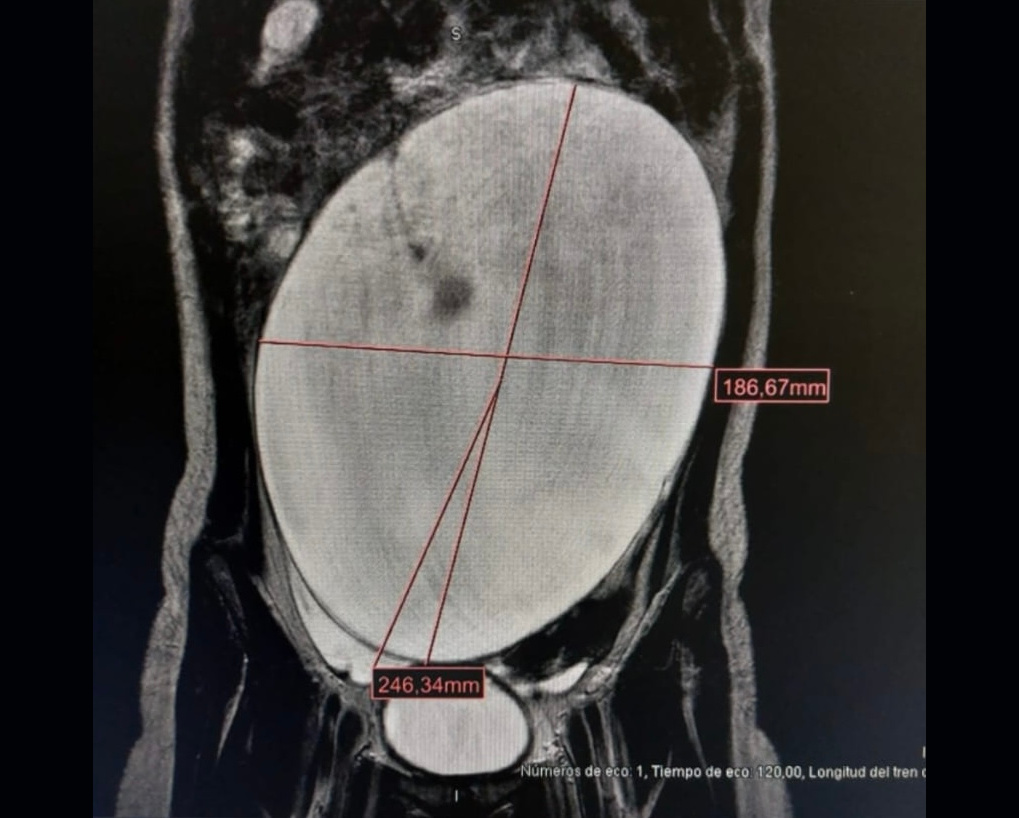

Además, se realiza ecografía abdominal, donde se objetiva una lesión quística en la cavidad abdominal. Se completa el estudio con una resonancia magnética, objetivándose lesión quística pélvica-intraabdominal de al menos 191 x 124 x 195 mm, con algún septo fino en su interior, dependiente del ovario izquierdo (Figura 2).

Figura 2. Resonancia magnética. Se observa imagen quística gigante en el abdomen, con algún septo fino.